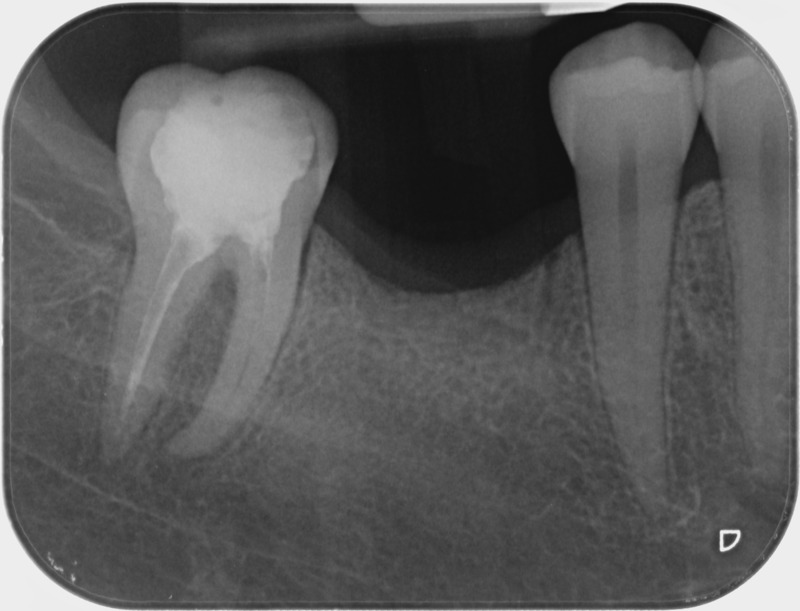

Avant

Après

• Traitement endodontique : Sous anesthésie locale et à travers la protection d’un champ opératoire nous accédons à la pulpe de la dent à soigner, puis aux canaux de ses racines que nous devons désinfecter. Ce soin nécessite l’élimination complète de la source de contamination (souvent la carie) parfois sous une ancienne reconstitution ou une couronne qu’il faut alors retirer. Une fois le nettoyage et la mise en forme des canaux réalisés, nous les obturons de façon hermétique avec un ciment et un matériau thermoplastique appelé Gutta Percha. Ceci afin d’empêcher une nouvelle prolifération bactérienne et d’assurer le maintien de la dent dans ses structures de soutien (ligament parodontal et os alvéolaire). L’ouverture effectuée au centre de la dent sera d’abord refermée avec un pansement provisoire avant d’envisager ensemble la reconstitution d’usage : un composite, un inlay-onlay ou une couronne.